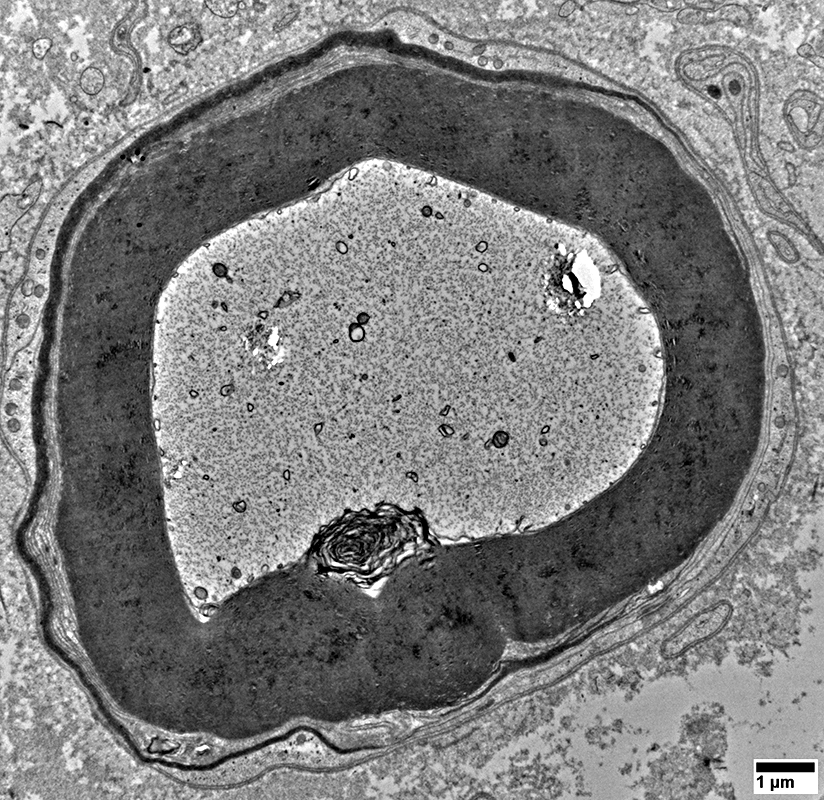

Lipid Droplets & Myelin debris segregated in different Schwann cell processes

From: R Schmidt

Cell Processes: Other